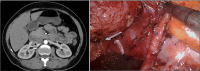

Castleman's disease is a distinct form of lymph node hyperplasia. It commonly presents as a mediastinal mass and rarely as a solitary retroperitoneal mass. We narrate a case of Castleman's disease presenting as a right suprarenal mass emphasising the usefulness of robot-assisted retroperitoneoscopy in surgical management of retroperitoneal masses in close relation to vital structures.